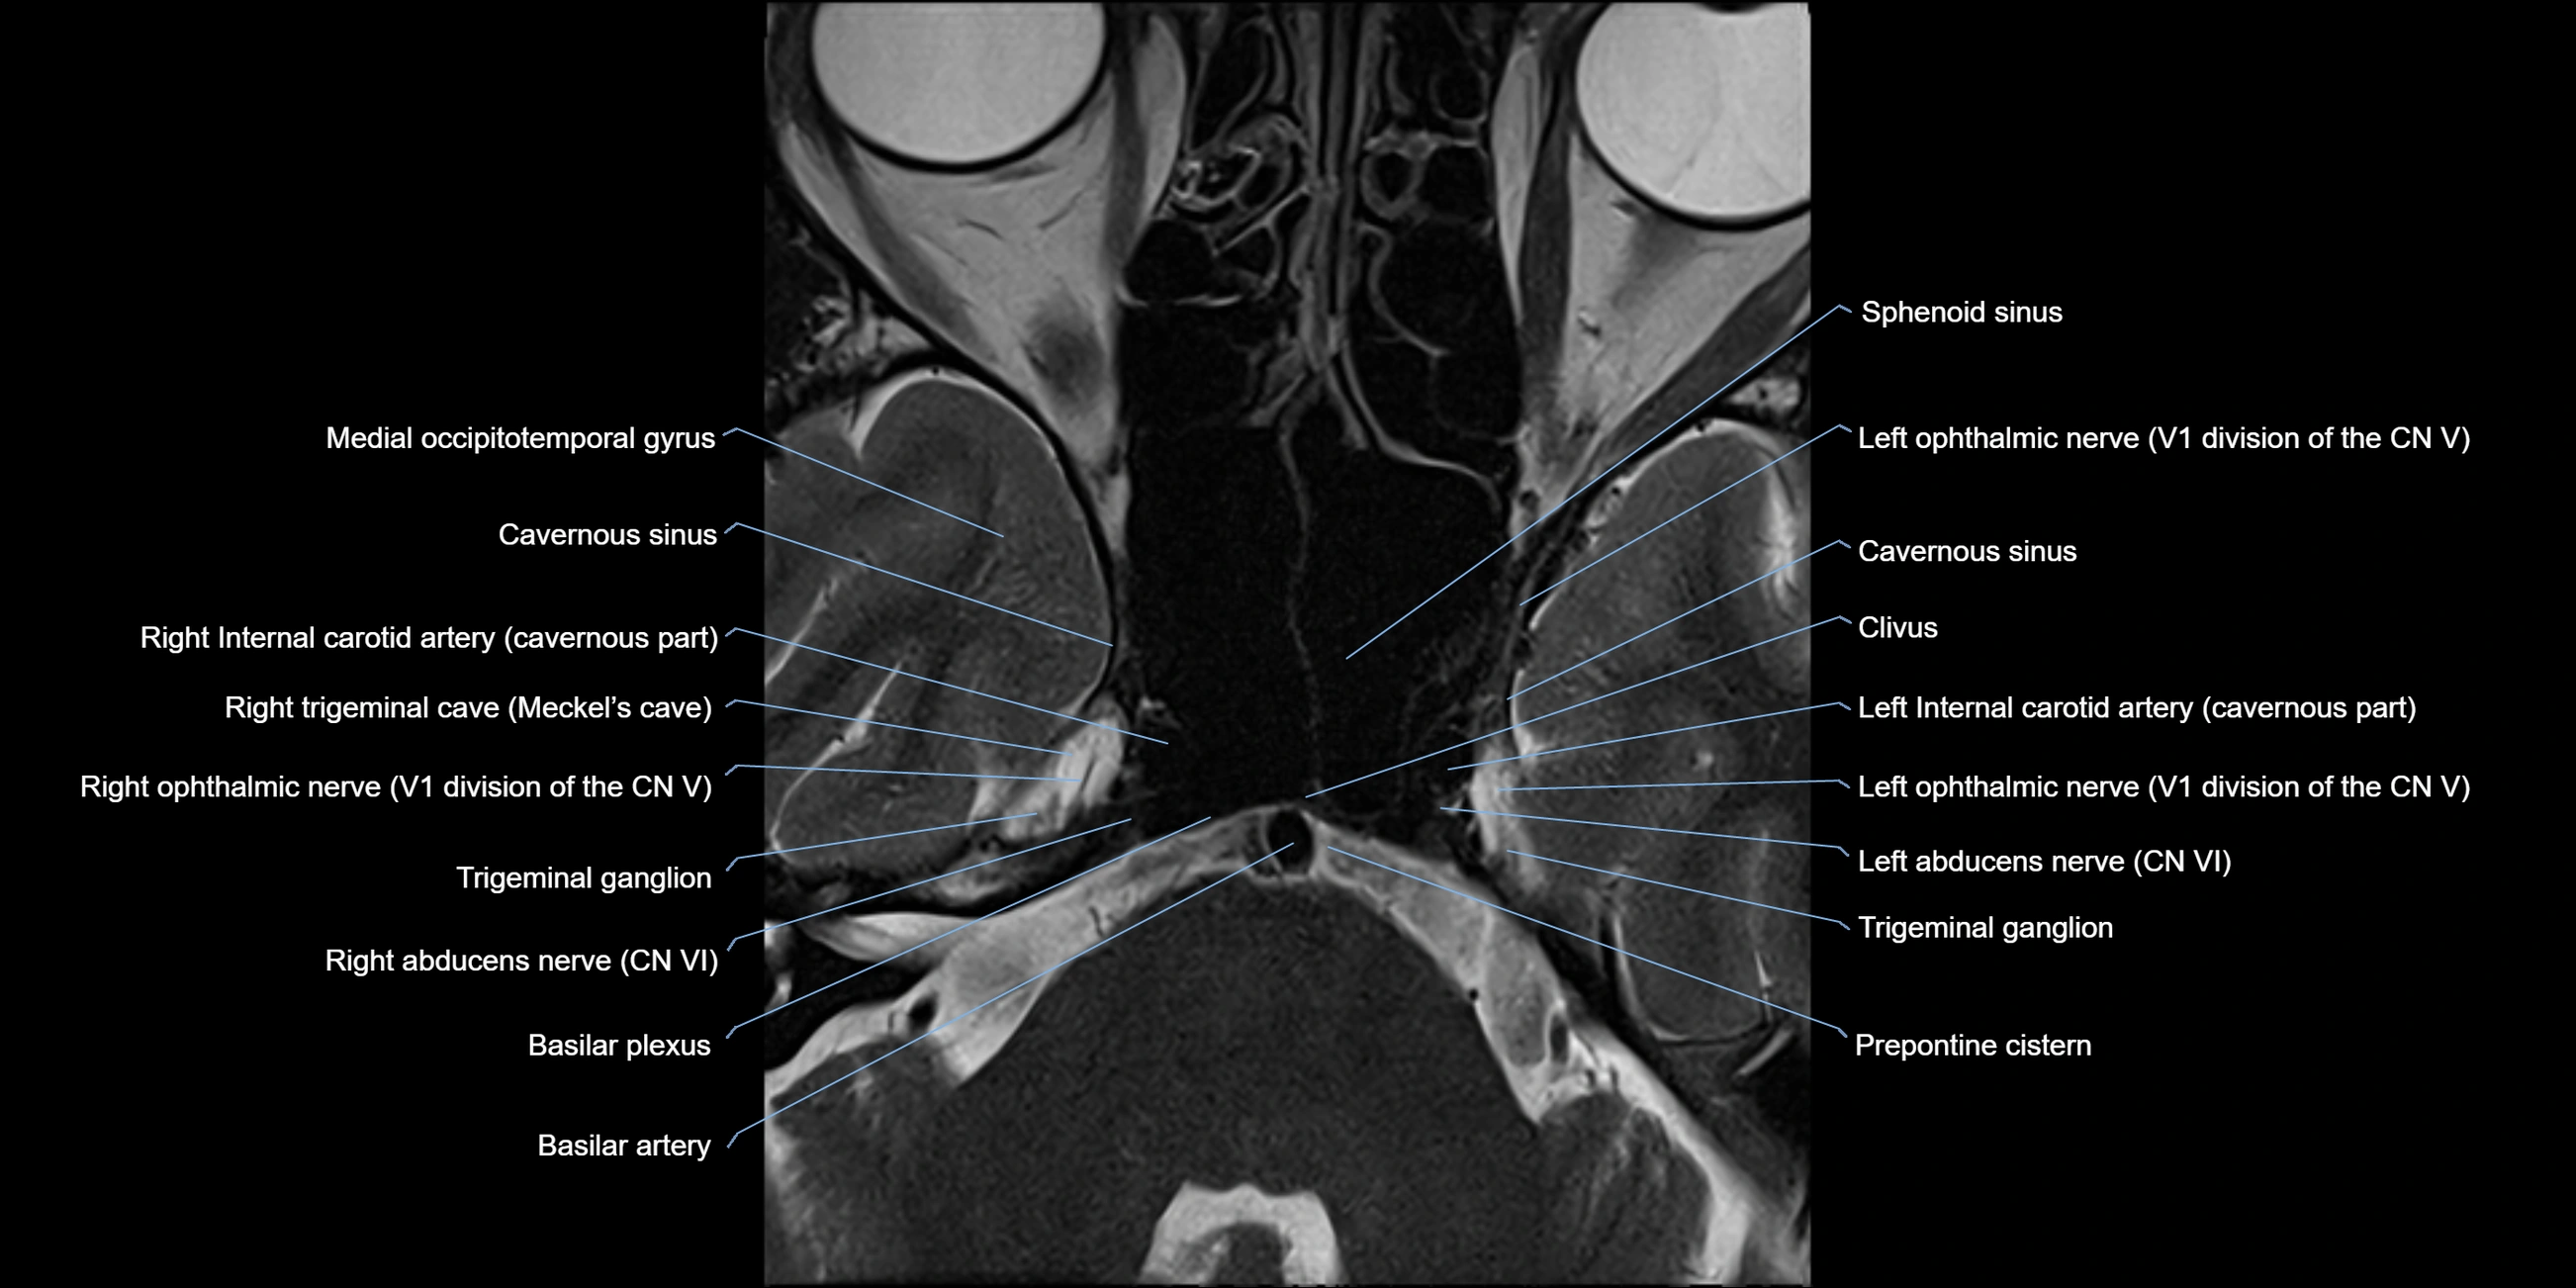

MRI Appearance

-

The abducens nerve is a small, thin, linear structure

Best visualized on high-resolution T2-weighted 3D MRI sequences (e.g., FIESTA or CISS)

Seen as a hypointense (dark) line running from the brainstem at the pontomedullary junction, traversing the prepontine cistern, and entering Dorello’s canal under the petrosphenoidal ligament, then into the cavernous sinus, and finally the orbit

May be challenging to visualize in standard MRI due to its small size

Pathology may be inferred by absence, displacement, or enhancement of the nerve

MRI images